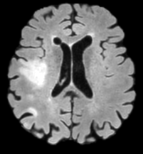

InputUNA-(a)UNA-(b)UNA-(c)UNA-(d)UNAGround TruthRefer to captionRefer to captionRefer to captionRefer to captionRefer to captionRefer to captionRefer to caption

Figure 6: Ablations on UNA’s healthy anatomy reconstruction.

To assess the contributions of UNA’s individual components, we perform an ablation study with several variants: (a) Training without fluid-driven anomaly randomization, i.e., training exclusively with real images with pathology; (b) Training with fluid-driven anomaly randomization, but initializing the anomaly profiles with random noise; (c) Training without contralateral-paired input, i.e., using only a single image without its contralateral counterpart; (d) Training without the intra-subject self-contrastive loss.

As shown in Figs. 6 and 4, training without fluid-driven anomaly randomization (UNA-(a)) results in the largest performance drop, showing only slight improvement over Brain-ID [38] (reported in Fig. 3), which does not train on diseased inputs at all. Introducing fluid-driven anomaly randomization improves overall performance, but performance gaps remain evident when compared to the proposed UNA when no real pathology profiles are used for initialization (UNA-(b)). Leveraging subject-specific contralateral information (UNA-(c), UNA-(d)) further enhances reconstruction results, particularly within diseased regions.